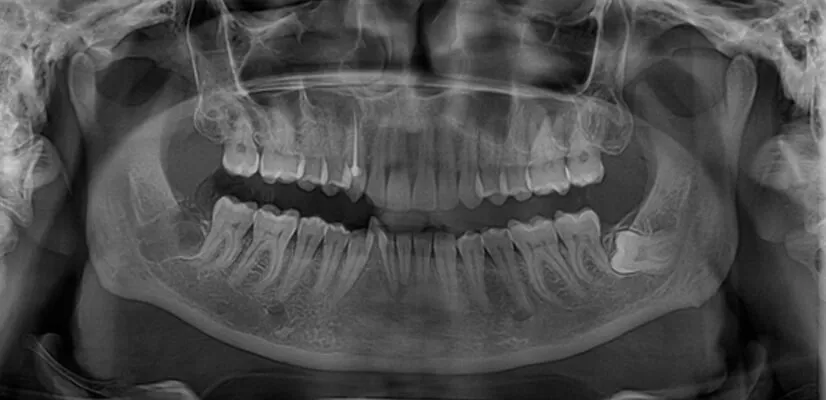

We have an in-house OPG and CT scan machine with which X-ray images are taken and a thorough examination of your mouth is done before making a treatment plan. An X-ray shows whether your teeth are impacted and if it has damaged other teeth and bone. If your teeth are impacted, our dentist is going to discuss with you the benefits and risks of surgical extraction.